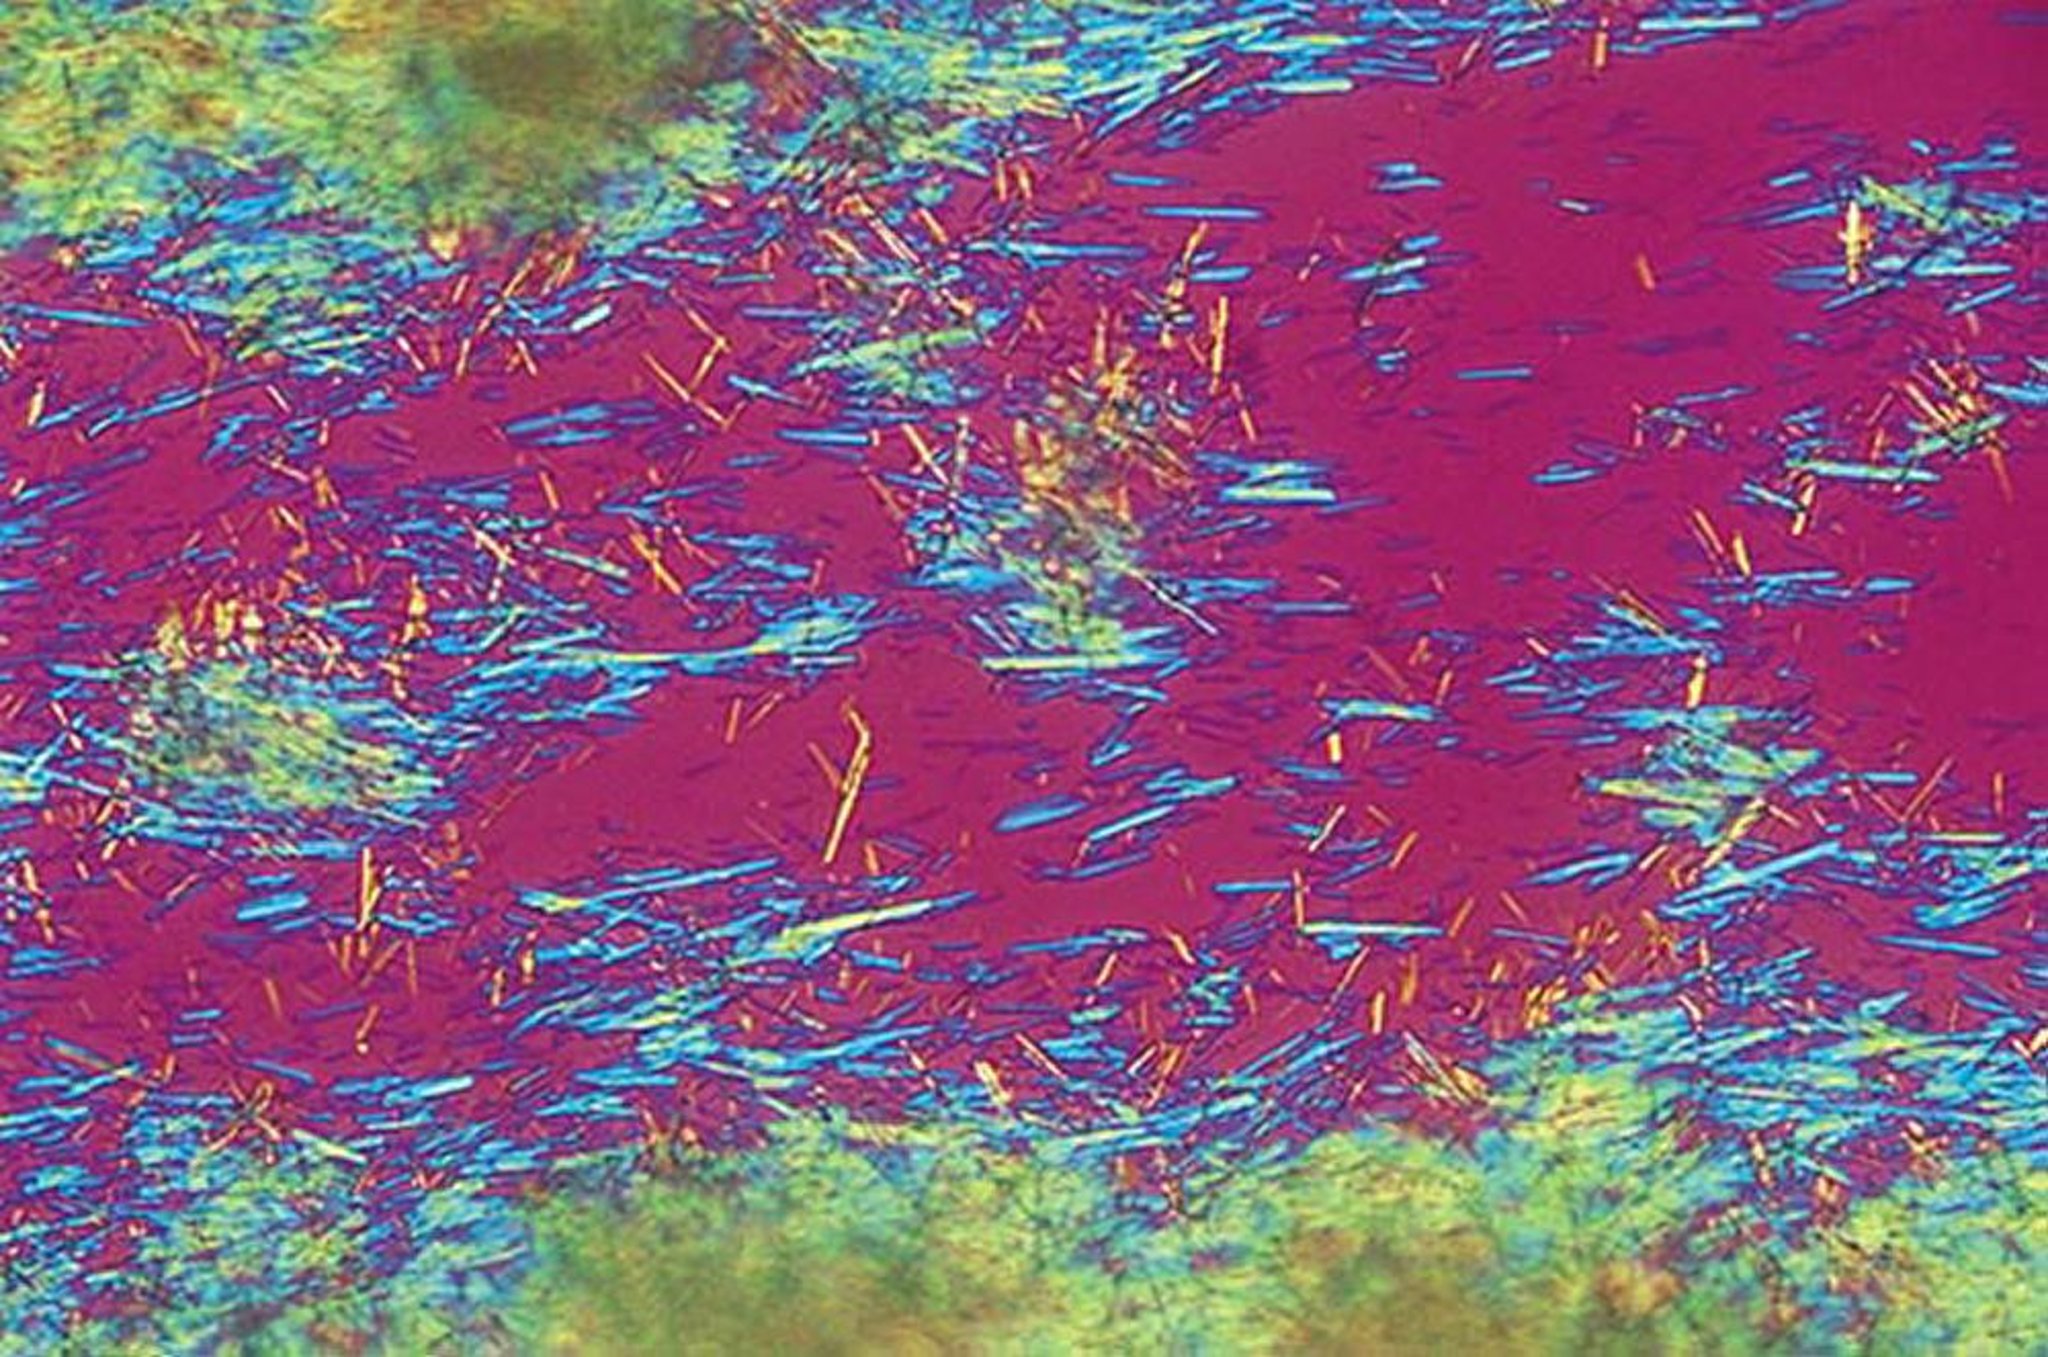

L'analisi del liquido sinoviale può confermare la diagnosi identificando cristalli aghiformi di urato, fortemente negativi alla birifrangenza, liberi nel liquido o inglobati dai fagociti. Il liquido sinoviale durante le riacutizzazioni presenta caratteristiche infiammatorie (vedi tabella Esame microscopico dei cristalli nelle articolazioni), normalmente 2000-100 000 globuli bianchi/mcL, con > 80% di globuli bianchi polimorfonucleati ( 5). Questi reperti si sovrappongono considerevolmente all'artrite infettiva, che deve essere esclusa con colorazione di Gram (che è insensibile) ed esame colturale ( 4).

• La diagnosi può essere confermata identificando cristalli aghiformi di urato, fortemente negativi alla birifrangenza, nel liquido articolare; o tramite TC a doppia energia o ecografia. La documentazione dell'iperuricemia non è sufficiente a confermare la diagnosi di artrite gottosa.